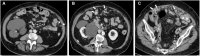

Management of peritoneal surface malignancies is currently entrusted to a multimodality approach. Computed tomography (CT) scan remains the first imaging method despite the limitations in identifying small implants in critical regions. Magnetic resonance imaging is usually recommended for its performance in small implants, mesentery, and small bowel assessment. Positron emission tomography/CT plays an important role only in pseudomyxoma peritonei. Thus, becoming aware of the imaging strengths and drawbacks and having a multimodality imaging approach might be the best option for the patients.